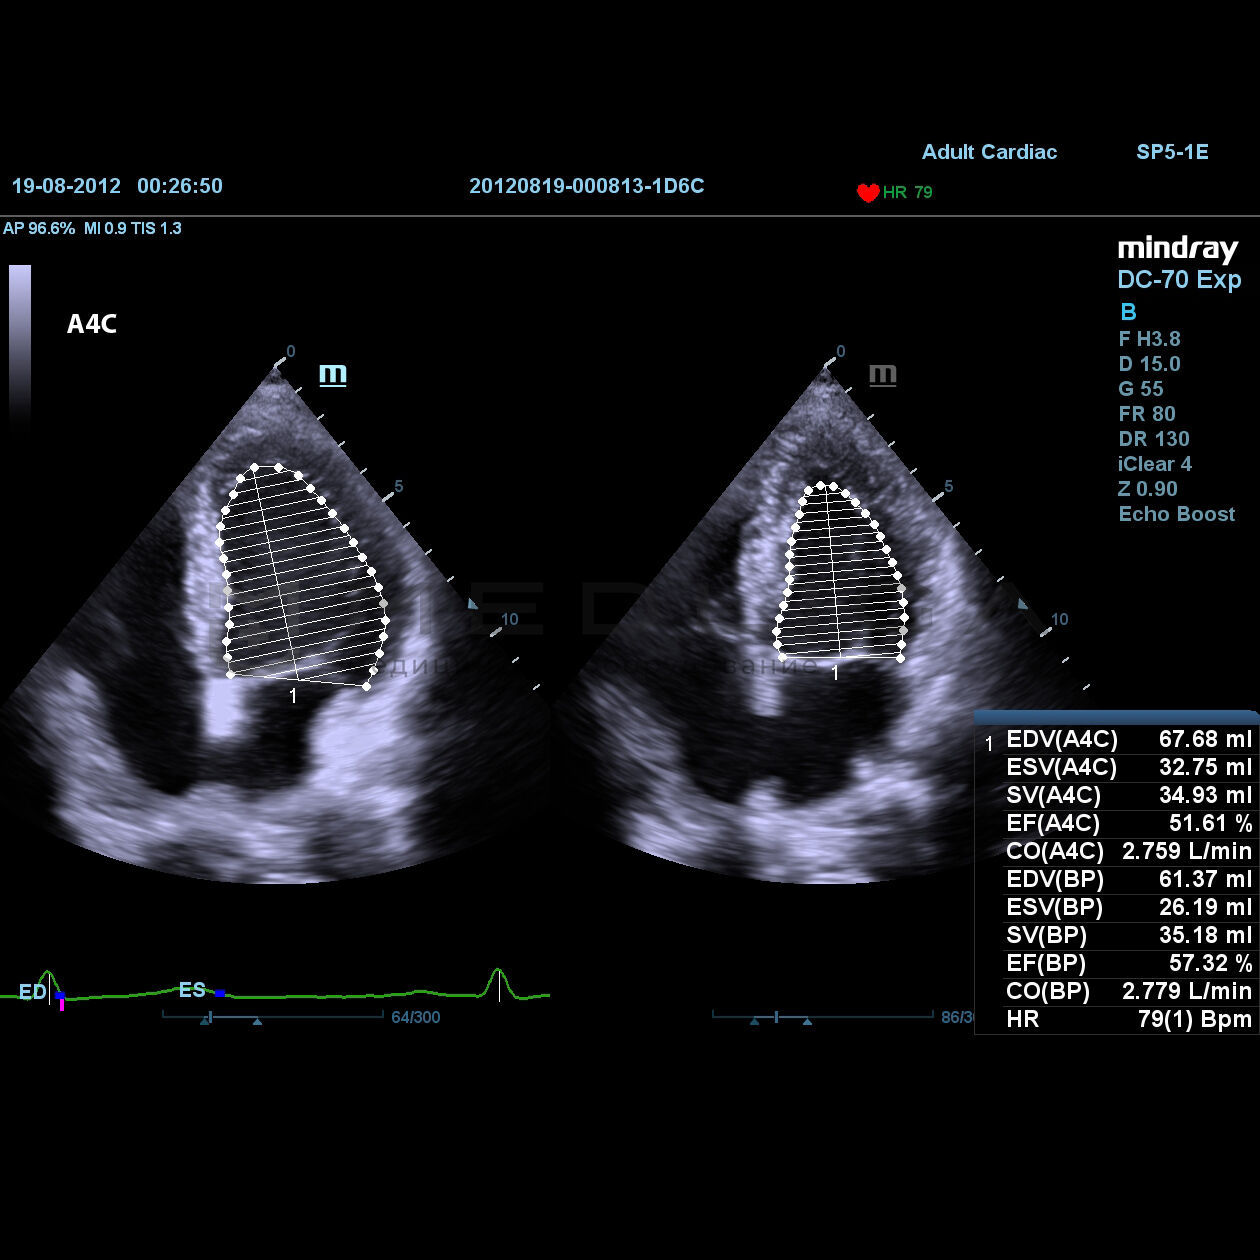

Auto EF - это интеллектуальный способ анализа изображений двухмерной эхокардиографии для автоматического распознавания диастолических и систолических кадров и вывода измерений для оценки функционирования таких параметров левого желудочка, как КДО, КСО и реакции выброса.

• Автоматическое распознавание А2C или А4С

• Автоматическое распознавание границы эндокарда

• Автоматическое распознавание диастолических и систолических значений